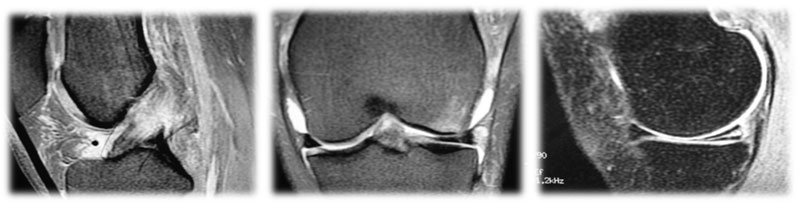

Lesões Meniscais do Joelho

Os meniscos são estruturas fibrocartilaginosas no joelho com diversas funções:

- Amortecimento

- Transmissão de forças

- Absorção de choque

- Estabilidade articular

- Lubrificação articular e nutrição

- Propriocepção

Pacientes com lesões meniscais frequentemente sentem dor na linha articular, associada a bloqueio articular e sensação de instabilidade (falseio).

Tratamento

A vascularização do tecido meniscal é crucial para o planejamento do tratamento. Apenas o terço periférico do menisco é vascularizado, o que significa que lesões fora dessa área têm baixo potencial de cicatrização. A preservação do tecido meniscal é fundamental para manter o equilíbrio articular. Mesmo em lesões com baixo potencial de cicatrização que exigem meniscectomia (remoção meniscal), busca-se remover a menor quantidade possível de tecido.